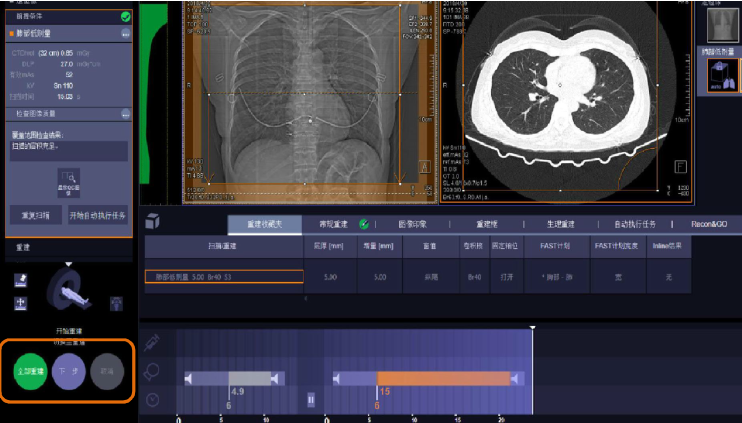

(2)确定扫描范围:根据临床要求确定扫描范围(图标1),然后点击“Go”(图标2)执行检查。

方舱ct怎么取西门子医疗方舱CT操作指南_https://www.jmylbn.com_新闻资讯_第10张